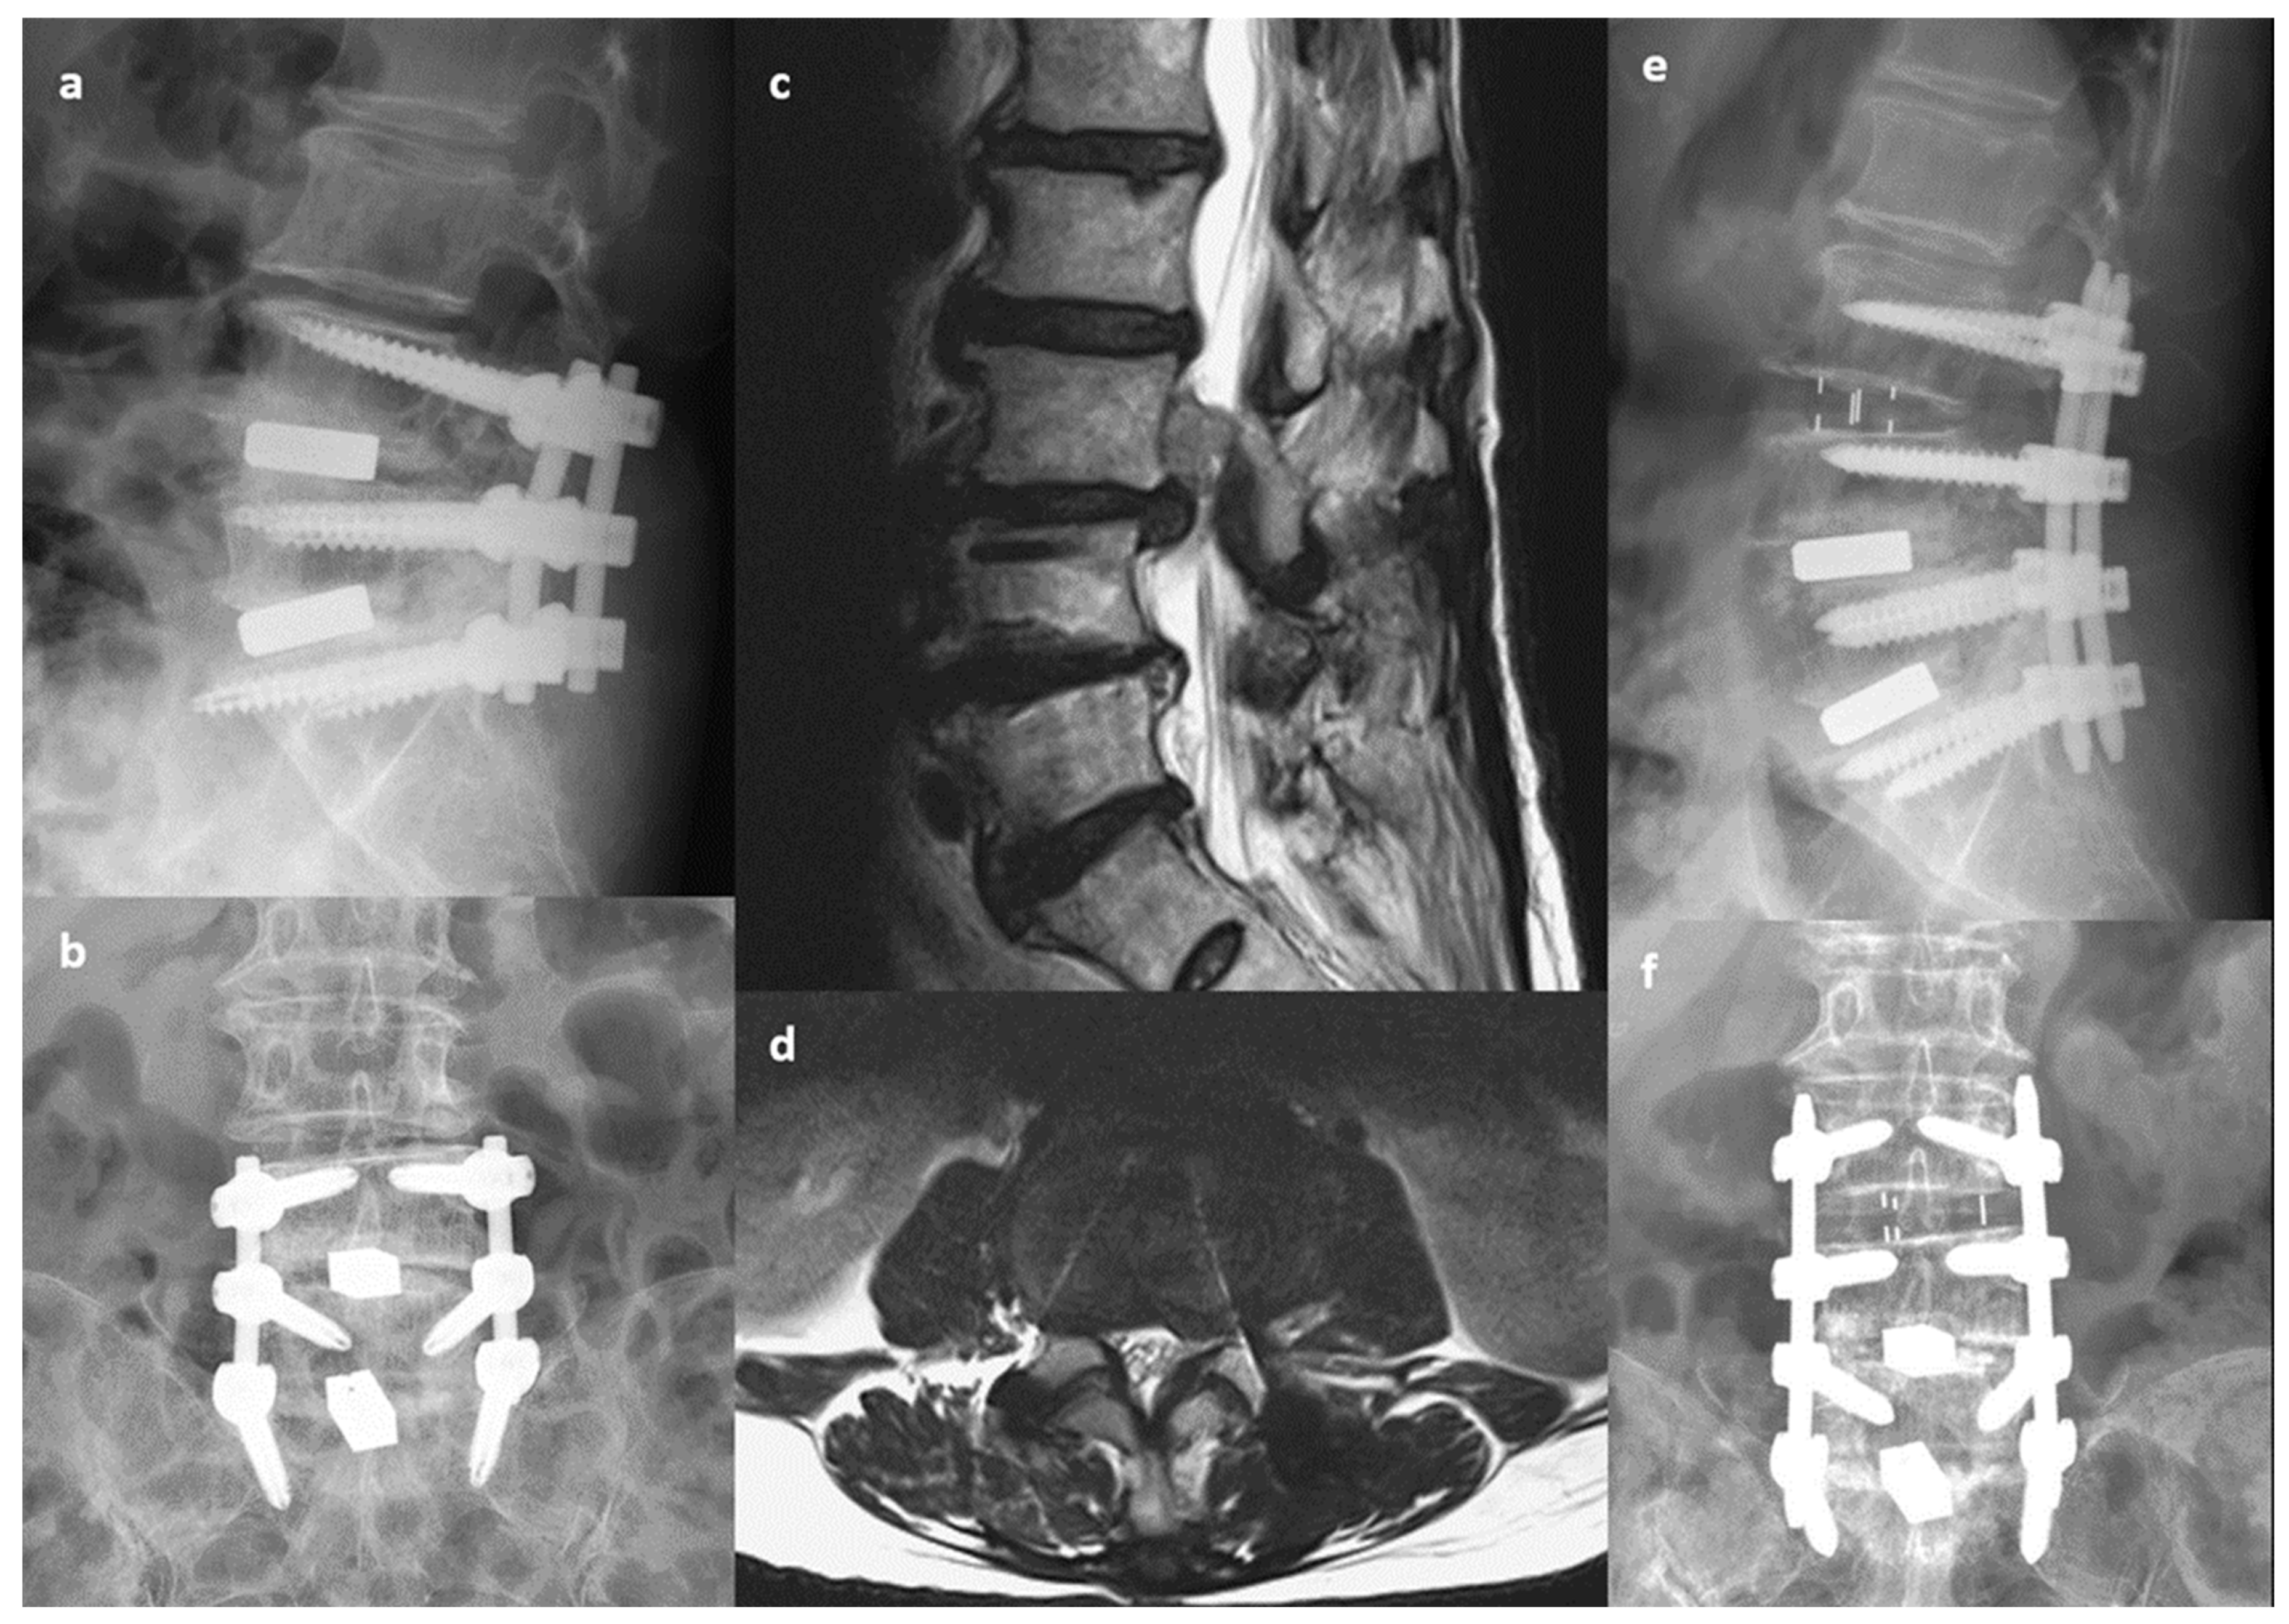

Figure 1.

A 78-year-old woman with low back pain and right thigh radiation. Primary transforaminal lumbar interbody fusion was performed 3 years previously to treat spinal stenosis and disc herniation at L4-5-S1. (a,b) Preoperative X-ray indicating decreased disc height at L3-4. (c,d) Preoperative MRI indicating uncontained disc extrusion with upper migration at L3-4. (e,f) Postoperative X-ray indicating oblique lumbar interbody fusion at L3-4 with extension of posterior instrumentation to L3. Left-side laminotomy of L3 was performed to remove the migrated disc.